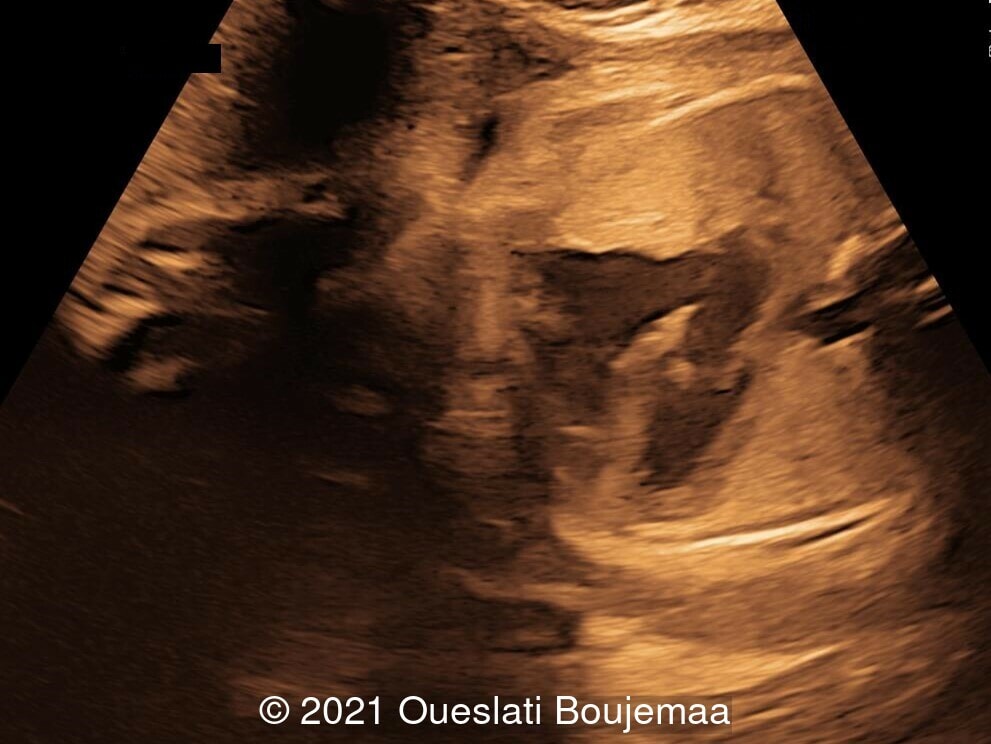

- Facial dysmorphism with retrognathia

- Cardiac malformation with ventricular septal defect and linear insertion of the atrioventricular valves